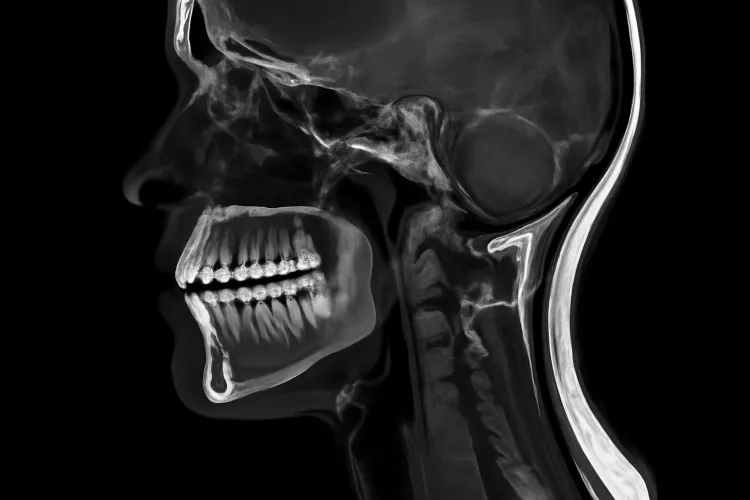

МРТ челюстного сустава — современный и безопасный метод диагностики, который становится всё более востребованным в стоматологии и челюстно-лицевой хирургии. Он позволяет выявлять патологии, недоступные для других методов, и играет ключевую роль в планировании лечения.

МРТ (магнитно-резонансная томография) использует магнитное поле и радиоволны для получения детализированных изображений мягких тканей, суставов, хрящей, связок и мышц. В отличие от КТ и рентгена, процедура не использует рентгеновское излучение, что делает метод безопасным для пациента. Диагностика особенно информативна при подозрении на заболевания височно-нижнечелюстного сустава (ВНЧС), опухоли, воспалительные процессы и аномалии развития.